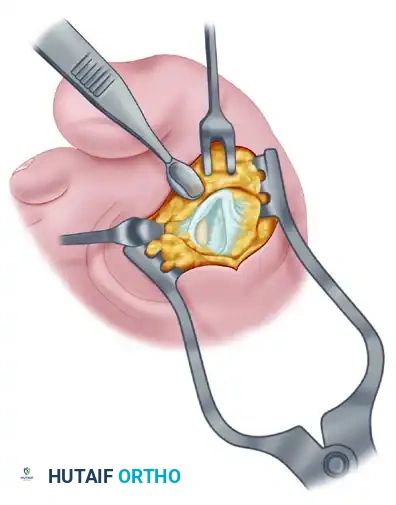

Fibular (Lateral) Sesamoidectomy: Plantar Approach

If the dorsal approach proves too difficult due to anatomical constraints, a plantar approach can be utilized for fibular sesamoidectomy.

- Have an assistant hold the ankle in dorsiflexion. A surgical headlight is highly recommended to visualize the full depth of the plantar wound.

- Flex and extend the hallux while palpating the plantar aspect of the foot to locate the sesamoid.

- Beginning 1.0 to 1.5 cm distal to the MTP joint, make a longitudinal incision on the plantar surface of the foot, extending proximally 3.5 to 4.0 cm between the first and second metatarsals.

- Separate the skin and fascial septa within the forefoot pad, and insert a small self-retaining retractor.

- Using small, blunt-tipped dissecting scissors, meticulously identify the neurovascular bundle to the first web space. Retract it laterally or medially, depending on the exact subluxated position of the sesamoid.

- Incise the plantar capsule and isolate the fibular sesamoid. Carefully shell it out from its soft tissue envelope, taking great care to protect the adjacent FHL tendon.